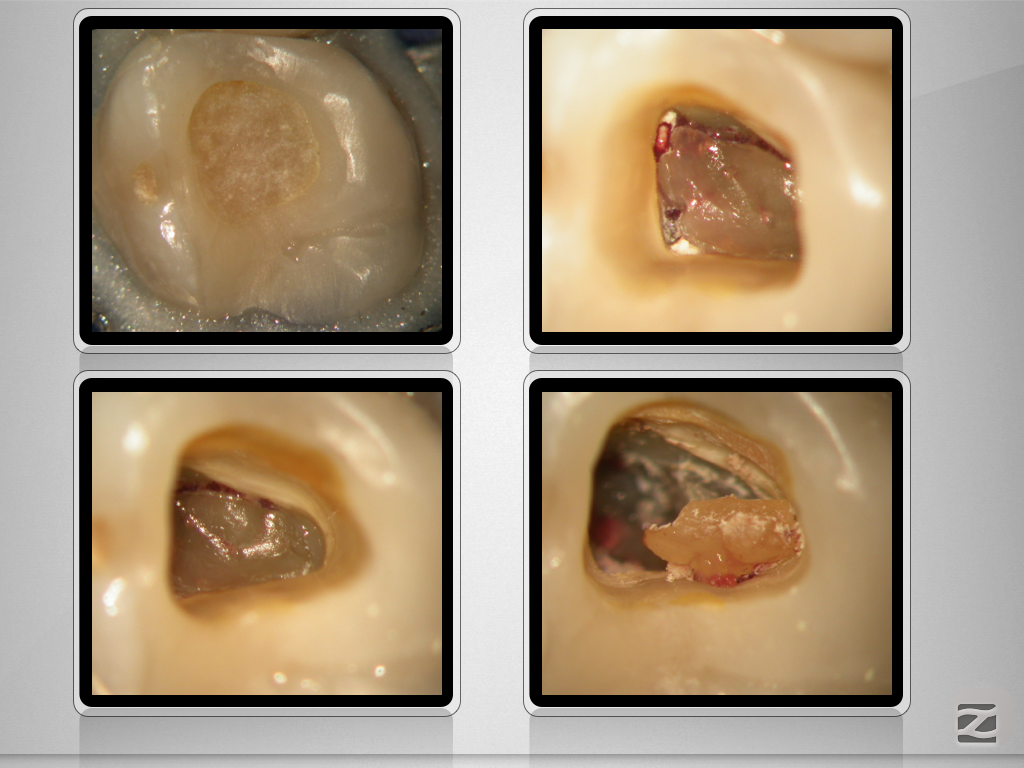

27d-neu-002

Vitales Gewebe – apikale Aufhellung